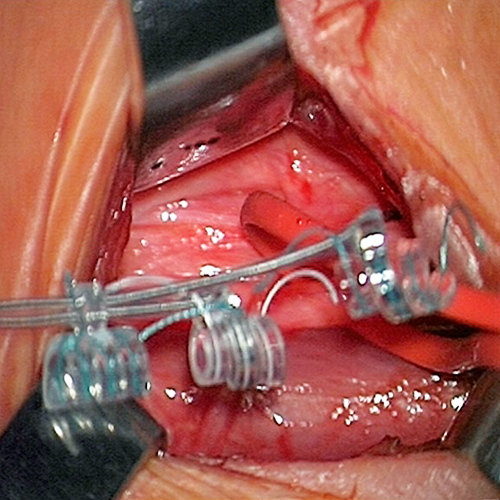

• Lesionectomía ampliada guiada con electrocorticografía:

• Para manejo quirúrgico de epilepsia de difícil control relacionada a displasias corticales, tumores del neurodesarrollo o gliomas de bajo grado y cavernomas.